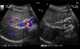

Gallbladder wall varices